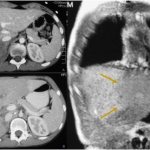

- Мрт и КТ легких. Эти виды диагностики помогают получить детальную информацию о патологии дыхательной системы и выявить трудноопределяемый прикорневой пневмосклероз.

Что такое пневмосклероз и каковы его признаки, хорошо показывает рентгенография. На снимках можно увидеть малейшие изменения, происходящие в легочной ткани, степень их выраженности и распространения. Метод помогает установить диагноз, когда нет выраженных симптомов при пневмосклерозе. На рентгенограмме, выполненной в прямой и боковой проекции, можно рассмотреть имеющуюся в легком опухоль.

По легочному рисунку и разветвлению бронхов определяют размеры пораженной области. Признаки пневмосклероза, выявленные с помощью рентгенографии, способны отразить симптомы сопутствующих заболеваний. В норме соединительная ткань на снимке отображаться не должна. Когда она увеличена, поверх легочного рисунка можно обнаружить ячеистость одного из следующих видов – мелкую, среднюю или грубую. Подобный рисунок означает наличие воспаления альвеол.

Когда есть необходимость изучения внутридольковой соединительной ткани, чтобы определить степень ее поражения, наряду с рентгенографией проводится томографическое исследование.

Выявить пневмосклероз помогает рентгенография. Исследование, как правило, дает вполне ясную картину:

- легочный рисунок деформируется из-за избыточного разрастания легочной ткани вокруг бронхов и в интерстиции;

- из корня исходят грубые тяжистые тени, постепенно исчезающие к периферии.

На каждом приеме врач производит общий осмотр пациента, с помощью которого предварительно оценивается состояние человека. При пневмоциррозе можно обнаружить деформацию грудной клетки, на которую обратит внимание не только врач, но и сам пациент. Аускультируя легкие, врач выслушивает ослабленное дыхание, влажные и сухие хрипы. Следует отметить, что такая аускультативная картина характерна для диффузного пневмосклероза, при очаговом пневмосклерозе результаты аускультации легких мало отличаются от нормы. Далее врач выписывает направление на рентгенологическое исследование легких. С помощью данного исследования удается обнаружить изменения в легочной ткани, оценить их распространенность и степень выраженности. На рентгенограмме выявляется усиление легочного рисунка, при циррозе определяется уменьшение в размерах пораженной части или целого легкого, за счет чего происходит смещение органов средостения в пораженную сторону. Нижние отделы легких могут приобретать вид пористой губки, в таком случае легкое называют «сотовым». Более детальную оценку о структуре легочной ткани дают КТ и МРТ.

Чтобы подтвердить диффузный пневмосклероз легких, проводится рентгенография или компьютерная томография, при помощи которых можно увидеть эмфизему, уменьшение объемов и рисунка органа.